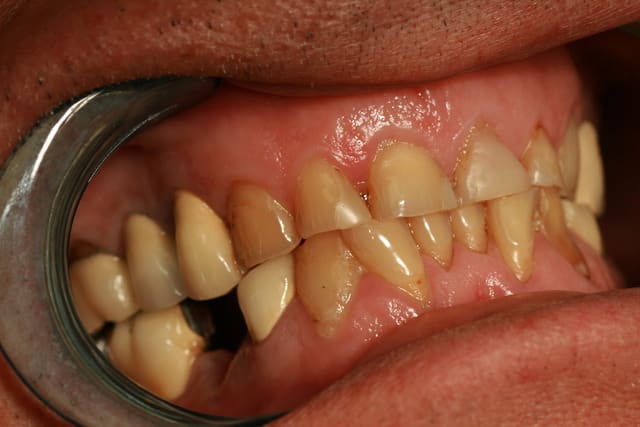

Petit dilemme j'ai un patient hyper bruxomane voir photo (qui ne supporte pas la gouttière ) il vient de perdre la 45 sur un bridge 44 45 47 avec inter sur 46.

1/ s'assurer de la pérennité de 47 (lésion apicale mésiale + épaississement ligamentaire + racines fortement fragilisées)

le bruxisme n'est pas une contre-indication à l'implantologie. il doit être traité ou tout au moins protégé par gouttière. je pense même qu'une solution sur 4 couronnes unitaires sera la plus fiable et la plus facile à manager en cas de casse. un bridge de 4 dent sur 2 piliers dentaires fragilisés comme ça, c'est 4 dents à remplacer dans peu de temps !

Un petit malin à voulu lui faire 2 bridge avec des pm faisant office de protection canine. Je pense que ce verrouillage est trop fort pour lui.

Or quand tu es trop verrouillé une gouttière ne peut te faire du bien au contraire puisque tu augmentes encore plus la largeur du bas .

Voilà pourquoi il ne la supporte pas .

on dirait qu'il avait une occlusion croisée pm style pm en rotation par ddd et que le dentiste lui a viré les pm pour faire un bridge protection groupe . tres a la mode dans les années 80 .bon on ne sait pas tres bien de quoi ça protegeait en fait ..

en tout cas le gonz n'avait plus sa liberté ,ni en avant ,ni sur les cotés .ça rend fou du matin au soir, et du coup il allait plus en avant pour prendre de l'espace libre .au moins il pouvait bouger en hyper propulsion bout a bout .et il a donc tout usé sauf l'inox qui s'est ecroui .ce type de gonz stimule tellement l 'os qu'ils n'ont trop pas de granulomes ou de pb paro ,l'os etant en perpetuel remaniement. ( bon signe pour les implants d'ailleur).par contre quand tu demontes un vieux bridge , dessous ç est souvent fragile comme du verre et ç est tout sec .mefi si on cherche a reprendre des ttt endo : a eviter le plus souvent.